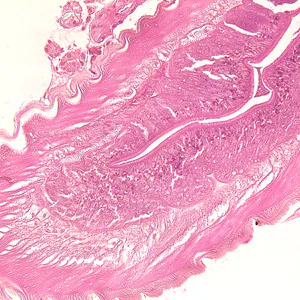

A 30-year-old who frequents sushi restaurants started experiencing severe gastritis, including epigastric pain, nausea and vomiting. He had reported eating at a sushi restaurant the previous day. After being admitted to the hospital for severe pain, a gastric biopsy was performed. A tissue specimen was sectioned and stained with hematoxylin and eosin (H&E). The attending pathologist observed unusual structures from the biopsied material and sent the slide to the CDC for diagnostic assistance. Figures A–C show structures observed on the slide; images were captured at 100x, 200x and 400x, respectively. What is your diagnosis? Based on what criteria?

Figure A